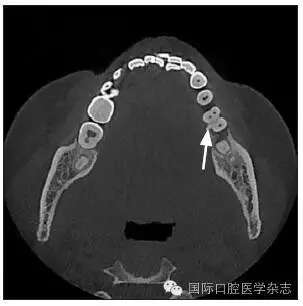

患者,女,42歲,因牙痛就診于中南大學(xué)湘雅醫(yī)學(xué)院附屬??卺t(yī)院牙體牙髓病科。臨床檢查為左側(cè)下頜第一磨牙遠(yuǎn)中齲,根尖壓痛和扣痛及頰側(cè)深牙周袋,牙髓電活力檢查陰性,近中根尖放射透明影。X線檢查根分叉區(qū)有不透明突起,扁形,

1.8 mm寬、8 mm長(zhǎng)(圖1~3)。

圖 1 根分叉釉珠

Fig 1 Enamel pearl in furcation area